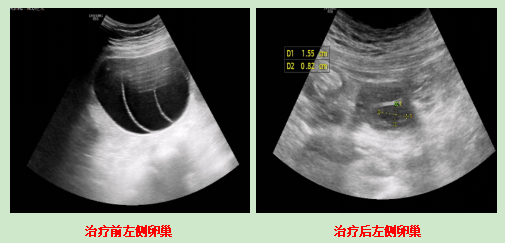

·卵巢B超:双侧都有囊肿,左侧7个多公分,右侧5个多公分。

·左侧卵巢那个7cm的囊肿,缩小到5cm左右。

·左侧卵巢囊肿只剩1公分多,右侧完全消失;